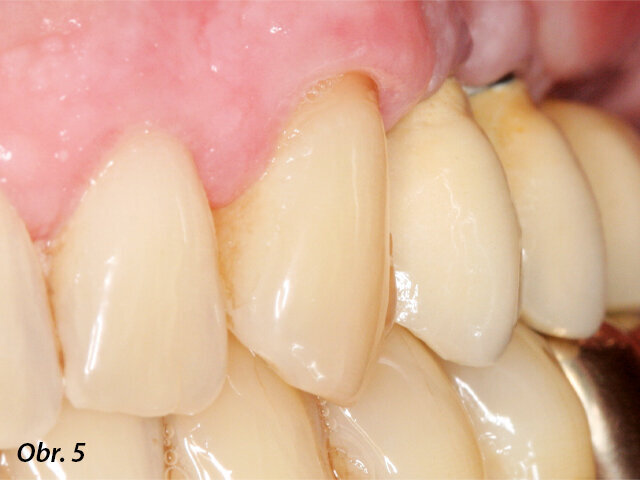

Bukální pohled na fixní částečnou náhradu.